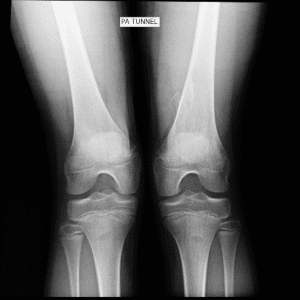

Pediatric Radiographs